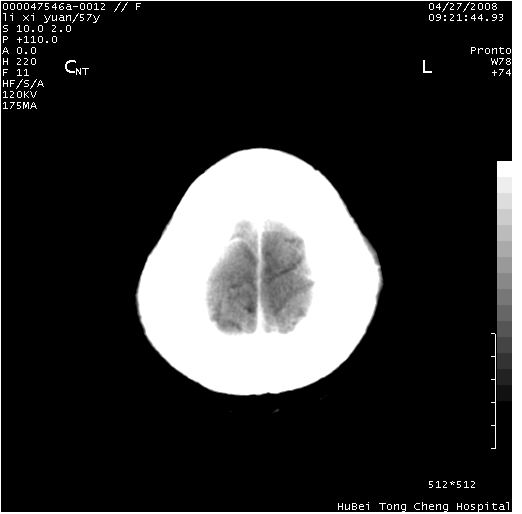

以下是引用zjzjr在2008-4-27 14:23:00的发言:[br]支持慢性炎性肉芽肿可能性大(增强效果较差).

以下是引用余辉在2008-4-27 14:02:00的发言:[br]病灶位于中央沟前方?位于额叶?高密度灶,灶周水肿不明显,病灶似沿脑沟走行,强化明显,局部层面呈现环状强化,考虑1脑表面血管性疾病,如血管瘤,血管扩张,灶内血栓形成,其次考虑肿瘤如脑膜瘤、转移瘤,胶母等

以下是引用形影不离在2008-4-27 14:13:00的发言:[br]考虑胶质瘤可能性大,不排除慢性炎性肉芽肿。建议mri检查。